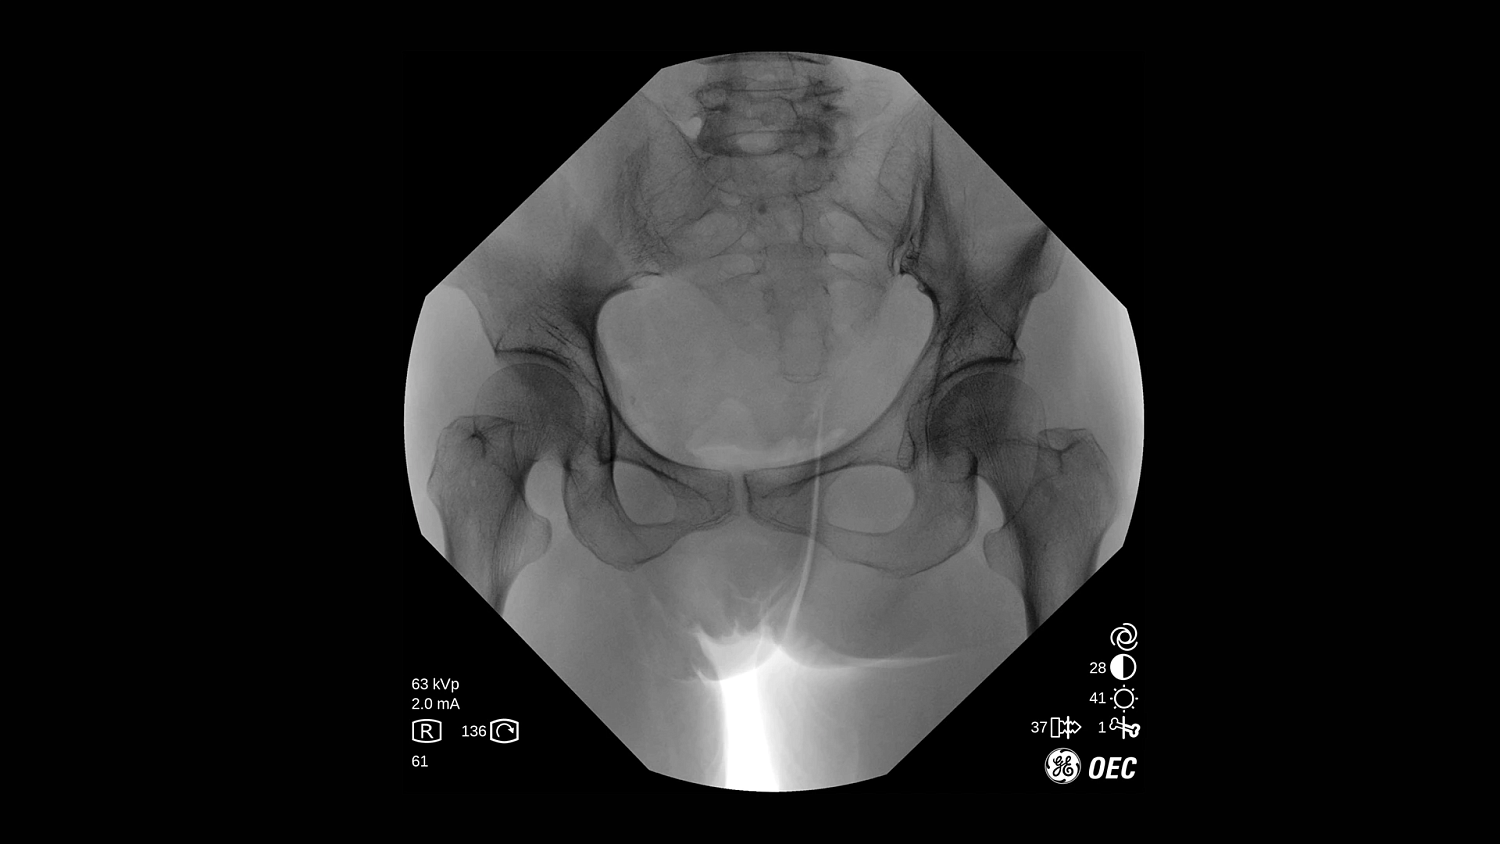

GE Healthcare OEC One CFD относится к классу мобильных рентгеновских аппаратов с С-образной дугой, в которых все ключевые узлы — излучатель, детектор, монитор и панель управления — объединены в единую компактную конструкцию. КМОП-плоскопанельный детектор и фирменная цепочка обработки Clear View обеспечивают высокую детализацию изображения в широком спектре клинических задач: от рутинных травматолого-ортопедических вмешательств до эндоваскулярных процедур и сложной спинальной хирургии. Интеллектуальные алгоритмы подавления помех от металлоконструкций, автоматической оптимизации окна и уровня, а также режимы увеличения позволяют уверенно визуализировать мелкие структуры, проводники и импланты без существенного роста дозовой нагрузки.

- Режимы рентгеноскопии, цифрового снимка и субтракционной ангиографии для интраоперационного контроля хода вмешательств.

- Специализированные клинические профили для ортопедии, спинальной хирургии, общей хирургии, урологии, сосудистых и болевых процедур.